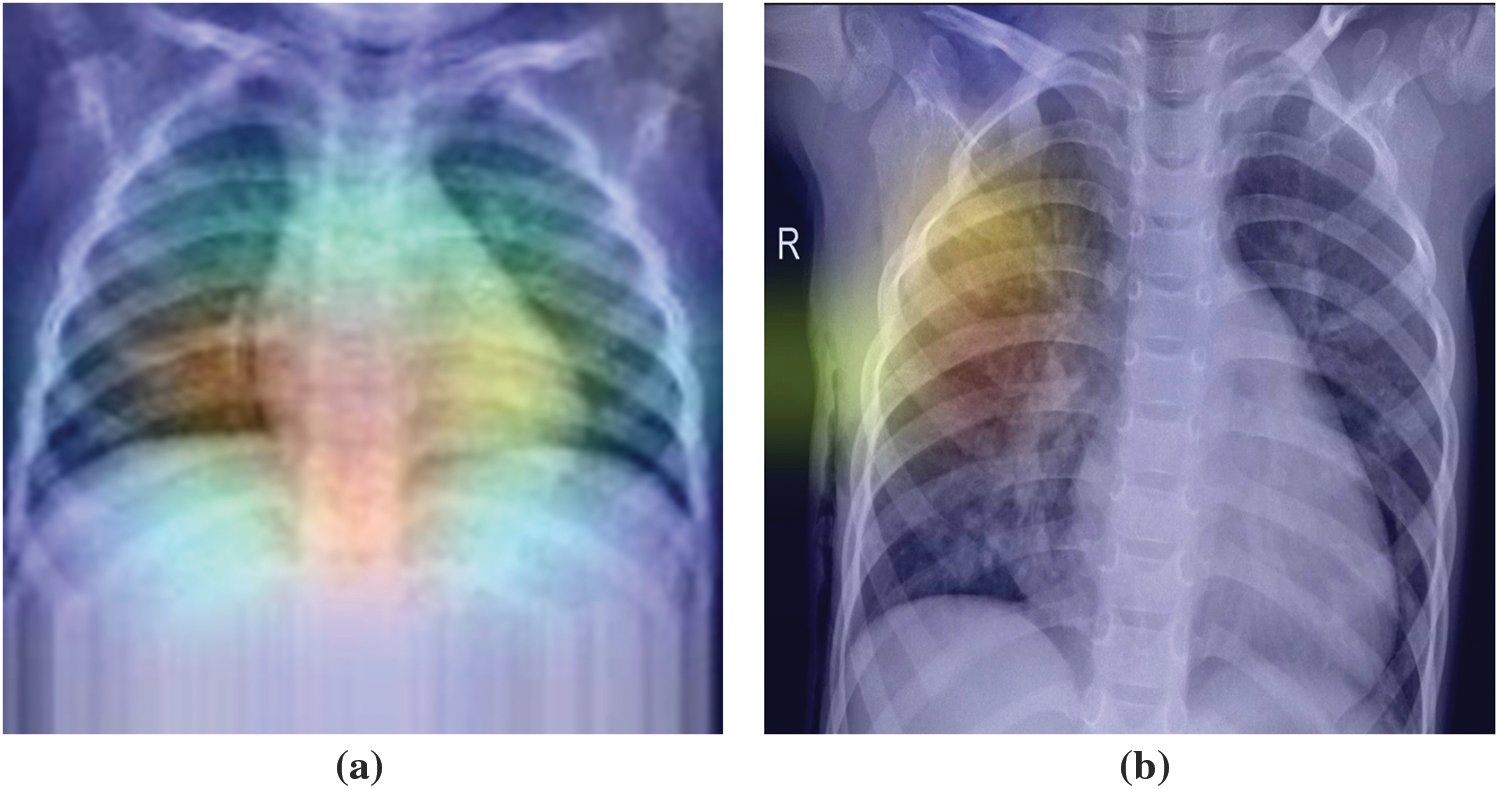

Superimposed visualization can be created by superimposing the heatmap onto the original image. Heatmaps are shown in Fig. 7. Superimposed images are shown in Fig. 8.

Figure 7: The highest value of heatmap is (a) in the center, (b) out of the center

Figure 8: The highest value of superimposed images is (a) in the center, (b) out of the center